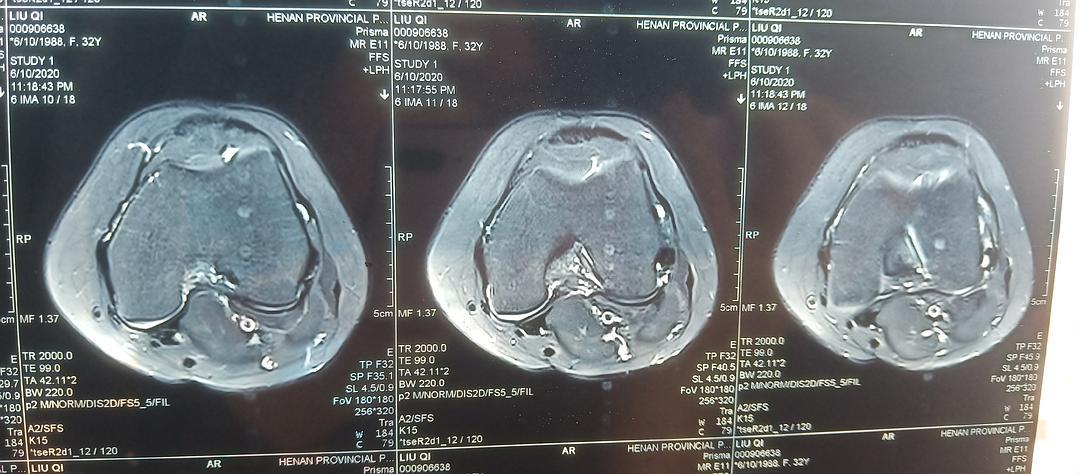

膝关节核磁共振读片

膝关节的核磁片子,半月板有损伤,自己也看不太懂,帮我

【关节影像】膝关节的磁共振(mri)解剖表现

磁共振成像优势---膝关节